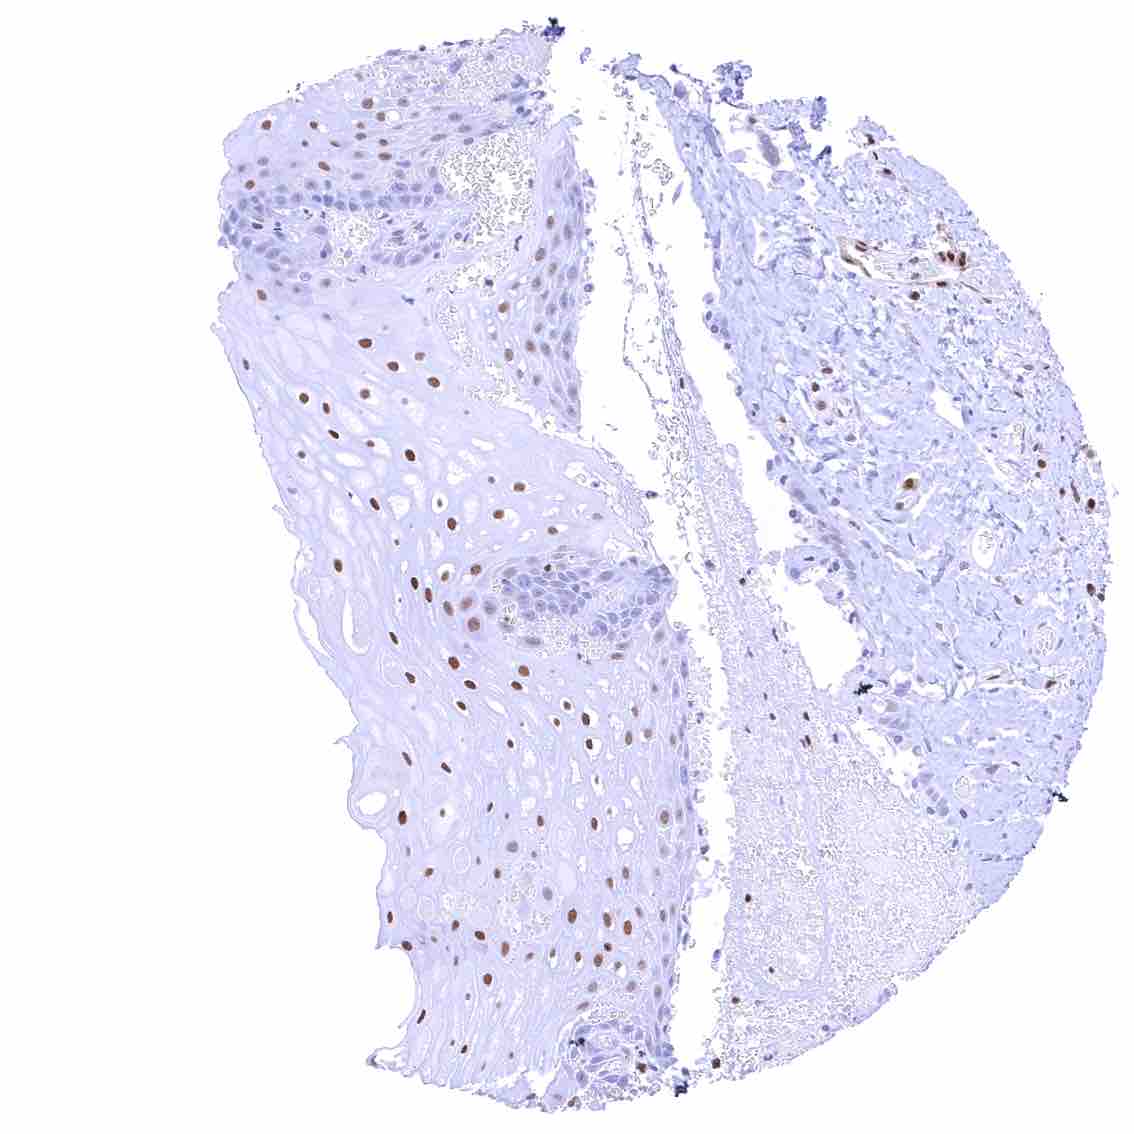

Uterus, ectocervix – Nuclear staining of squamous epithelial cells predominates in the more mature cell layers (top 50_ of the epidermis).